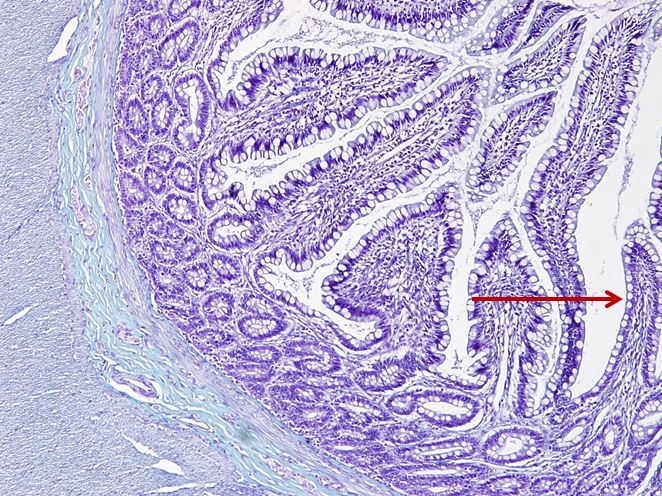

HỖNG TRÀNG:

Tầng niêm mạc:

Biểu mô: trụ đơn có vi nhung mao

Lớp đệm: tuyến Lieberkühn

Cơ niêm: liên tục

Tầng dưới niêm mạc: van ngang